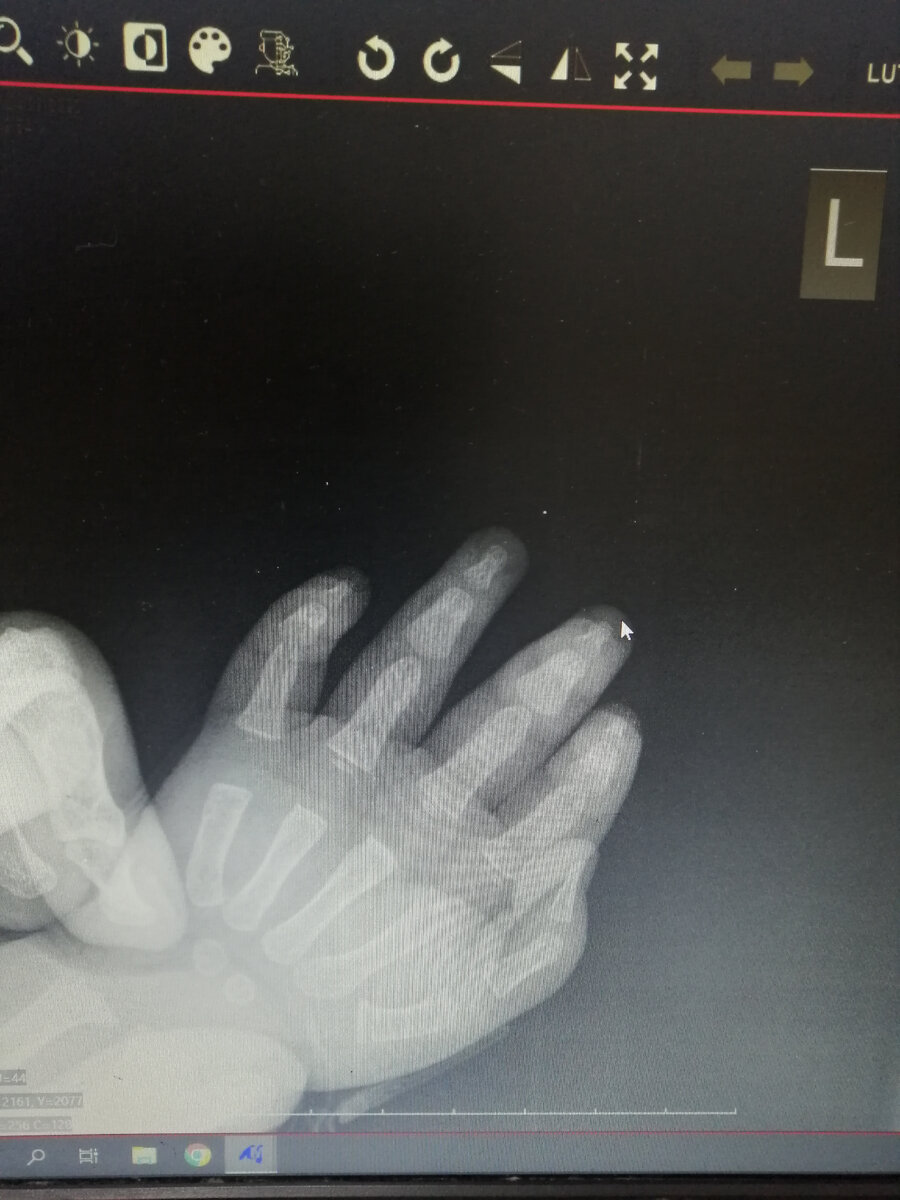

Лаборант милая молодая и, главное, спокойная женщина. Муж остаётся в кабинете, я в коридоре готовлюсь к ещё одной порции плача ребёнка. Но его нет, они там мило беседуют, делают два снимка (третий в таком возрасте только в экстренных случаях) и муж слышит уже привычное для нас "какой у вас спокойный и терпеливый ребёнок".

Попросили сфотографировать снимок, теперь кричит на меня из галереи телефона - "как ты могла?!"